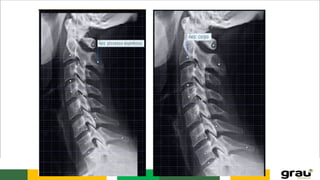

C. CERVICAL (C3-C7)

Forame transversário

C4

Processo espinhoso bifurcado

C. CERVICAL

C7 (transição)

Espinhos mais

proeminente

Semelhante a vértebra

torácica